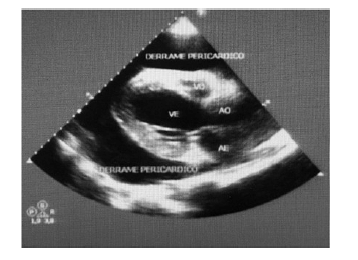

Considere um paciente de 58 anos de idade, etilista, com hipertensão arterial e doença renal crônica. Apresenta irregularidade nas sessões de terapia renal substitutiva e comparece a consulta médica com histórico de batedeira, ortopneia, PA = 89 mmHg x 43 mmHg; FC = 126 bpm; SatO2 = 95% (ar ambiente), FR = 26 ipm, ausculta pulmonar limpa e ausculta cardíaca quase inaudível. Encaminhado para sala de ecofluxo, retorna com o ecocardiograma mostrado: dilatação acentuada do átrio esquerdo e moderada do VE; hipertrofia excêntrica do VE; função sistólica do VE deprimida em grau moderado; hipocinesia difusa do VE; insuficiência mitral discreta; e derrame pericárdico de grau acentuado com sinais ecocardiográficos de aumento das pressões intrapericárdicas – sinal de “swimming heart”.